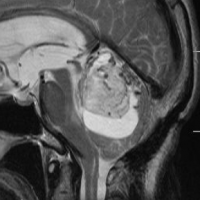

- MRIでは,のう胞(袋に水がたまったようなもの)を高頻度に認めます

- 腫瘍の本体は造影剤で増強効果をうけて白く丸く映ります

- 腫瘍はたいてい丸くてはっきりした形にみえます

左小脳にできた小さな のう胞性血管芽腫です。矢印の先にある小さな塊だけが腫瘍で周囲は腫瘍から染み出した液体が溜まっています(のう胞といいます)。右側は血管撮影とMRIを組み合わせた画像で,腫瘍に動脈が流入しているのが見えます。